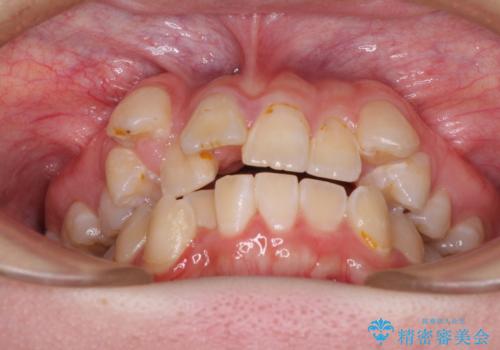

転位歯や埋伏歯などの難易度の高い抜歯矯正治療

- 八重歯や埋伏している奥歯など、多くの難しい問題を抱えている患者様です。

重度叢生のため、大臼歯をしっかりと咬合させるために、下顎は左右第二小臼歯を、上顎は前歯部の叢生を解消するために左右第一小臼歯を抜歯し、口元の突出感を改善するために、上顎大臼歯が前方に移動しないようにするために、補助装置による架強固定を行うこととしました。

叢生は思ったよりも早期に改善されましたが、舌の突出癖による上下前歯の非接触が全く改善されず、2年間ほど治療期間が延びる結果となってしまいました。